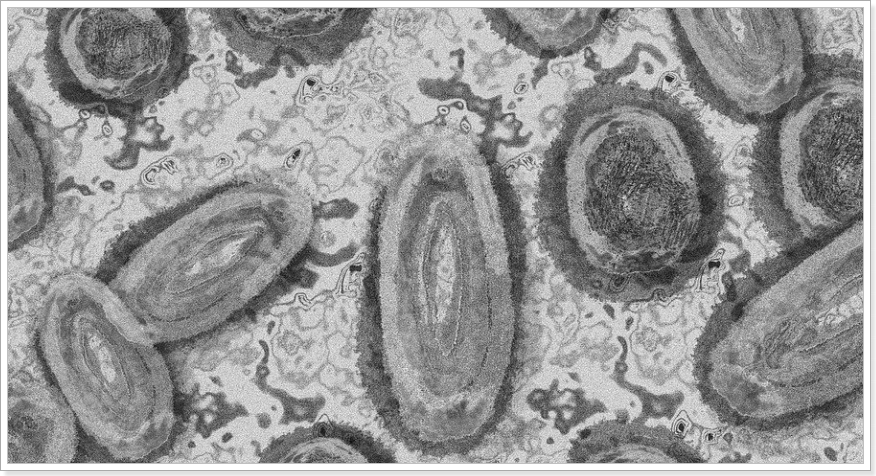

원숭이두창이란 어떤 질병인가?

*2022년 6월 '원숭이두창' 2급감염병으로 지정!